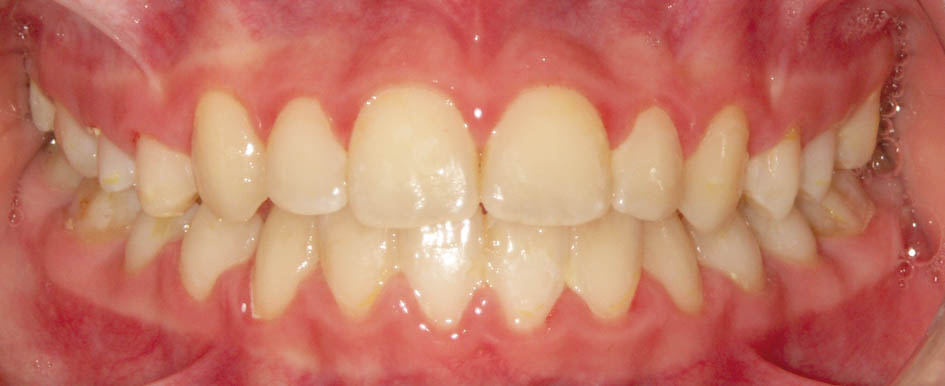

بعد از آن بایستی صبر کنیم تا تمام دندانهای دائمی رویش یابند (شکل 43-5 الی 45-5). با چنین کار سادهای شما از کلاسIII شدن، تنگی ماگزیلا، انحراف طرفی مندیبل (بخاطر کراس خلفی یک طرفه) و انحراف قدامی مندیبل (بخاطر کراس قدامی دندانها) جلوگیری میکنید. اگر قادر به اینگونه درمانها نباشید چنین بیماری دارای عوارض بسیاری میشود و در بزرگسالی نیاز به چندین عمل جراحی خواهد داشت و معمولاً نتایج درمانهای جراحی به زیبایی چنین کارهای ساده ارتودنسی (شکل 46-5) نمیشوند.

شکل 43-5: تکمیل رویش دندانهای قدامی با اکلوژن کلاسI در سمت راست

شکل 44-5: اکلوژن کلاسI در سمت چپ

شکل 45-5: میدلاین صحیح بیمار فوق پس از درمان